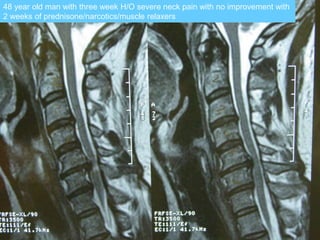

48 year old man with three week H/O severe neck pain with no improvement with

2 weeks of prednisone/narcotics/muscle relaxers